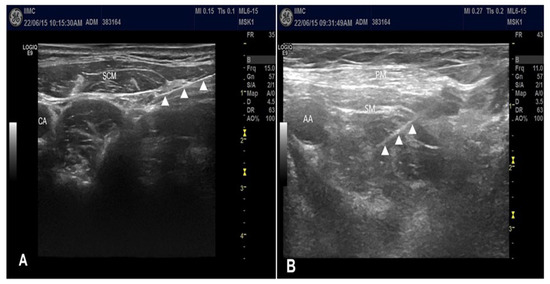

CPB was performed first followed by CCB. First, intermediate CPB was performed under ultrasound guidance without a nerve stimulator since the cervical plexus is a sensory neural plexus. The patients were placed in a supine position with arm adducted, and the head was turned to the contralateral side. A linear transducer was placed at the posterolateral aspect of the neck in transverse orientation. The needle was inserted at the midpoint of the posterior border of the sternocleidomastoid muscle. After administration of 1 to 2 mL of 2% lidocaine to anesthetize the skin using a lateral-to-medial in-plane technique, a 5 cm block needle was positioned in the intermuscular plane between the sternocleidomastoid and scalene muscles (Figure 1A) [11], which often provided visualization of the superficial cervical plexus. After negative blood aspiration, 5 mL of 0.5% ropivacaine was slowly injected.

Subsequently, CCB was performed. Patients were placed in a supine position with the ipsilateral arm abducted. Initially, the transducer was placed directly over the middle third of the clavicle in the transverse orientation. The transducer was moved caudally and placed transversely below the middle third of the clavicle. The axillary artery was identified beneath the subclavian muscle in the costoclavicular space. The brachial plexus was identified as a compact group of nerves located lateral to the axillary artery below the clavicle. After sterilization with an antiseptic solution, a stimulating needle was advanced using an in-plane approach from the lateral to medial direction and positioned at the center of the brachial plexus cords (Figure 1B) [12]. The nerve stimulators were set at 0.5 mA, 0.1 ms, and 1 Hz. The needle position was adjusted when the motor response decreased below a stimulation of <0.3 mA. Following a negative blood aspiration, 20 mL of 0.5% ropivacaine was slowly injected in increments.

Figure 1. (A) Ultrasound-guided intermediate cervical plexus block; (B) ultrasound-guided costoclavicular brachial plexus block. ▲ indicates needle shaft. AA, axillary artery; CA, carotid artery; PM, pectoralis major muscle; SCM, sternocleidomastoid muscle; SM, subclavius muscle.